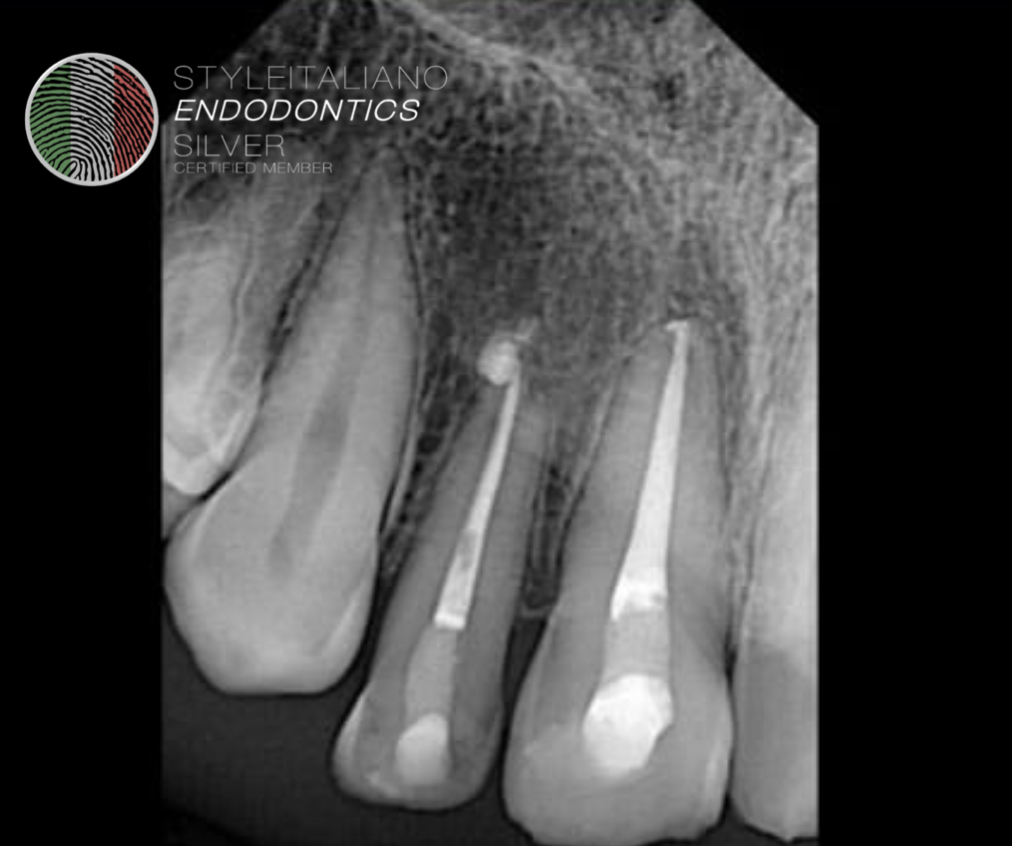

Fig. 2

Tooth was carefully extruded with the help of luxators and forceps about 4mm inside the socket. And splinted with the help of wire.